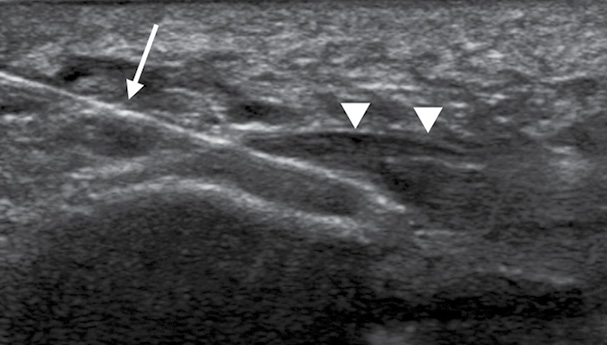

Dr. Lee’s research demonstrated the effectiveness of platelet-rich plasma injections in treating plantar fasciitis. Right: A 53-year-old woman with refractory plantar fascitiis (arrowheads). Longitudinal ultrasound image showing in-plane needle placement (arrow) into the plantar fascia during the platelet-rich plasma injection.